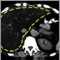

Hepatomegaly is swelling of the liver beyond its normal size.

If both the liver and spleen are enlarged, it is called hepatosplenomegaly.